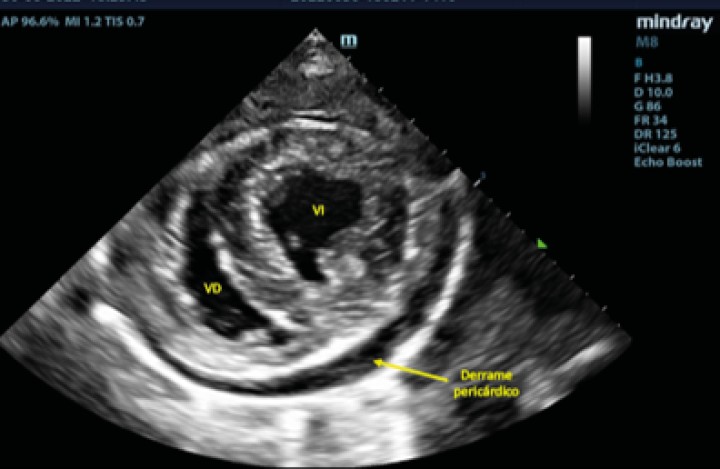

Ecocardiográficamente se observó una dilatación severa del atrio izquierdo (AI) (ratio aorta/atrio izquierdo[ Hansson K, Häggström J, Kvart C, Lord P. Left atrial to aortic root indices using two-dimensional and M-mode echocardiography in cavalier King Charles spaniels with and without left atrial enlargement. Vet Radiol Ultrasound 2002; 43(6): 568-575. [PubMed] ] de 3,88; diámetro normalizado del atrio izquierdo[ Marchesotti F, Vezzosi T, Tognetti R, et al. Left atrial anteroposterior diameter in dogs: reference interval, allometric scaling, and agreement with the left atrial-to-aortic root ratio. J Vet Med Sci 2019; 81(11): 1655-1662. [PubMed] ] de 26,91) y dilatación del ventrículo izquierdo (diámetro interno del ventrículo izquierdo normalizado en diástole[ Cornell CC, Kittleson MD, Della Torre P, et al. Allometric scaling of M-mode cardiac measurements in normal adult dogs. J Vet Intern Med 2004; 18(3): 311-321. [PubMed] ] de 2,28) secundarios a un engrosamiento, fallo de coaptación y prolapso de las valvas de la válvula mitral, determinando una regurgitación mitrálica posterior grave. Se realizó radiología torácica para valorar la presencia de edema pulmonar, observando un patrón intersticial-alveolar severo en el área perihiliar y en los lóbulos caudales pulmonares, compatible con la presencia de edema pulmonar de origen cardiogénico. Tras la realización de la radiografía torácica, se diagnosticó ECDVM en estadio C[ Keene BW, Atkins CE, Bonagura JD, et al. ACVIM consensus guidelines for the diagnosis and treatment of myxomatous mitral valve disease in dogs. J Vet Intern Med 2019; 33(3): 1127-1140. [PubMed] ] agudo, con una puntuación ecocardiográfica de la insuficiencia mitral (MINE)[ Vezzosi T, Grosso G, Tognetti R, et al. The Mitral Insufficiency Echocardiographic score: A severity classification of myxomatous mitral valve disease in dogs. J Vet Intern Med 2021; 35(3): 1238-1244. [PubMed] ] de 12. No se observó derrame pericárdico durante la realización del examen (Figs. 1 y 2).

<p>Corte paraesternal derecho 4 cámaras, previo a la rotura del atrio izquierdo. VI: ventrículo izquierdo; VD: ventrículo derecho; AI: atrio izquierdo; AD: atrio derecho.</p>

Figura 1

Corte paraesternal derecho 4 cámaras, previo a la rotura del atrio izquierdo. VI: ventrículo izquierdo; VD: ventrículo derecho; AI: atrio izquierdo; AD: atrio derecho.